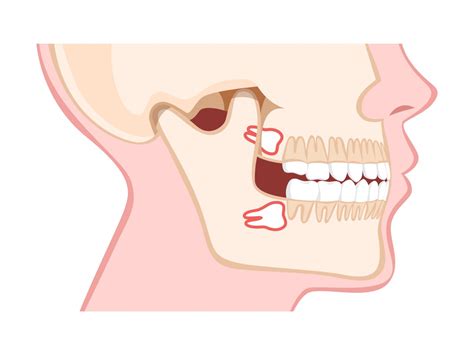

When these teeth begin to develop, they form at the very back of the dental arch. Because they are the last to erupt, they often encounter a space crunch. If there is insufficient room, the teeth become impacted. An impacted tooth is one that is unable to break through the gum line or emerge fully because it is blocked by adjacent teeth, soft tissue, or bone. This is a primary reason why dental professionals often recommend monitoring their growth via routine X-rays long before they cause symptomatic pain.

Complete Bony Impaction The tooth is entirely encased in the jawbone. Surgical extraction by a specialist.

Furthermore, removing problematic 3rd molar teeth protects your other teeth. When these molars grow at an awkward angle, they can push against your second molars, causing overcrowding, misalignment, or even decay due to the difficulty of cleaning the tight spaces between them. By addressing these teeth early, you preserve the integrity of your overall dental health, potentially saving yourself from more invasive orthodontic or restorative treatments later in life.